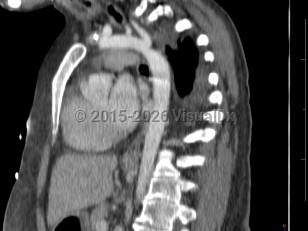

Coarctation of the aorta

Narrowing of the descending aorta distal to the take-off of the great vessels. Posterior costal arteries and internal mammary and scapular arteries provide collateral flow to the descending aorta. Usually congenital, although can be acquired as a consequence of inflammatory diseases affecting the aorta (eg, Takayasu arteritis). Clinical manifestations vary by age and associated cardiac defects, which may include bicuspid aortic valve, atrial septal defect (ASD), ventricular septal defect (VSD), patent ductus arteriosus, and D-transposition of the great vessels.

Aortic coarctation accounts for 5%-8% of all congenital heart defects and may occur as an isolated defect or in combination with ventricular septal defect and bicuspid aortic valve. Infants typically present with signs of heart failure as the ductus arteriosus closes due to significant increase in afterload with left ventricular strain and pulmonary congestion.

Previously undiagnosed children and adults typically present with hypertension. Systolic pressures are usually higher in the upper extremities than in the lower extremities. Femoral pulses are usually diminished or delayed. Lower extremity claudication occurs with exertion. Lower extremity systolic pressures may be unobtainable.